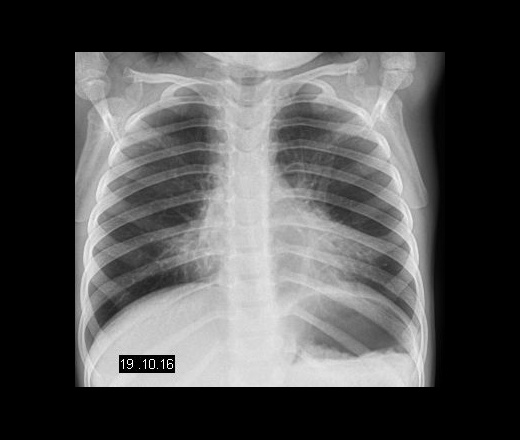

Как выглядит снимок легких при коклюше: примеры и пояснения